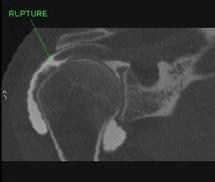

On comprend bien qu’en cas de rupture transfixiante de la coiffe, le liquide migrera de l’articulation vers la bourse sous acromio-deltoïdienne et qu'ainsi, le diagnostic sera facilement établi !!!

- si la rupture partielle concerne seulement la partie profonde du tendon, une image par addition (communiquant avec l'articulation gléno-humérale opacifiée) sera visible à l’arthroscanner et le diagnostic pourra alors être fait.

- Si la rupture concerne par contre la partie superficielle du tendon, il n’y aura pas de liquide dans l’articulation gléno-humérale, mais un épanchement dans la bourse sous acromio-deltoïdienne. L’arthroscanner, s’il n’est pas complété secondairement par une opacification de la bourse, passera alors complètement à côté de cette rupture non transfixiante !!!